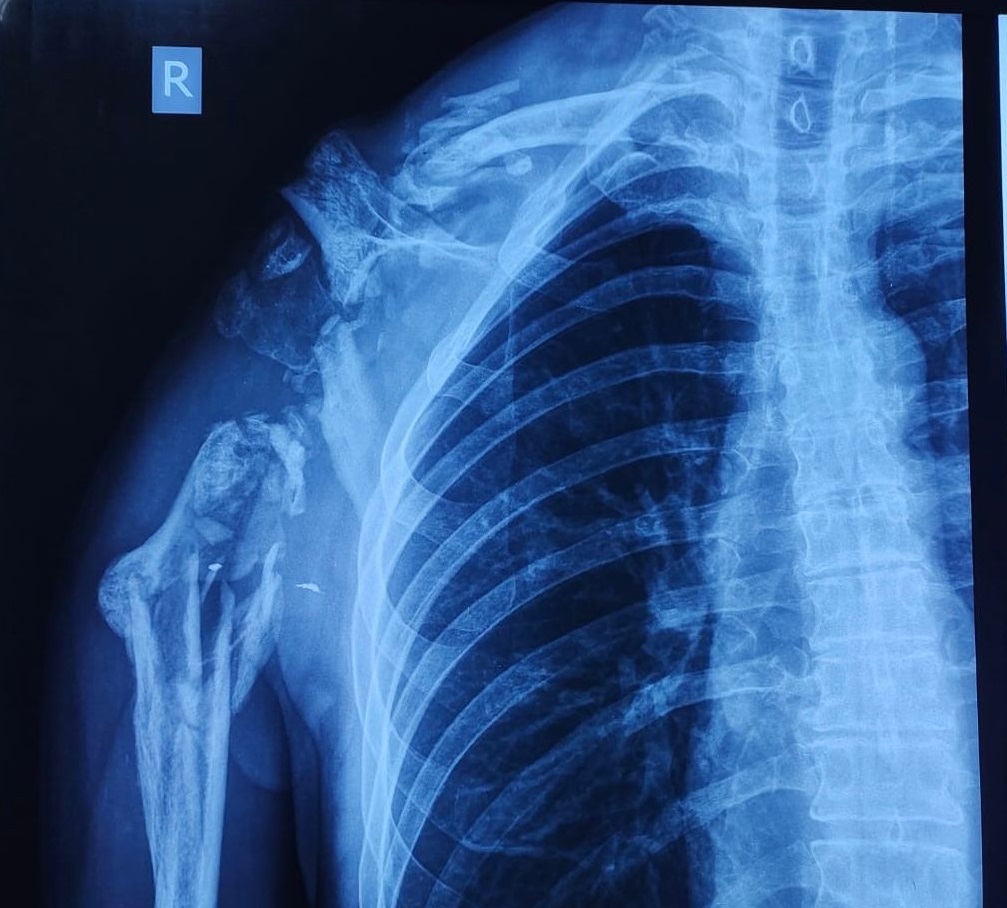

Але не лише кісток. Як розказав кореспондентці АрміяInform начальник травматологічного відділення підполковник медичної служби Юрій Лазаренко, уже влітку минулого року до лікувального закладу почали надходити захисники із дуже важкими пораненнями м’язового компонента плечового поясу із масивними дефектами кісткової тканини верхньої кінцівки.

— Якщо говорити просто, у хлопців за рахунок значних пошкоджень унаслідок поранення відсутня частина м’язів чи кістки, у деяких випадках — вирвано суглоб. Ушкодження великої ділянки м’яких тканин не дозволяє робити навіть протезування. Тож ми зіткнулись із проблемою: як замістити ці дефекти та відновити функції руки.

— До нас привезли пацієнта, морського піхотинця, із важким пораненням плеча: у нього була відсутня середня частина кістки, вирвано велику ділянку м’язів, але збережений суглоб. Йому пощастило, що на попередніх етапах лікування йому не ампутували руку. Ми самі, якщо чесно, спочатку вагались щодо вибору шляхів лікування. Та, врешті, ухвалили рішення рятувати кінцівку. Для нього був виготовлений 3D-титановий імплант. Але попередньо ми зі спини перемістили м’язи зі шкірою на плече. Згодом встановили імплант. За три місяці після операції воїн вже доволі непогано міг рухати рукою.